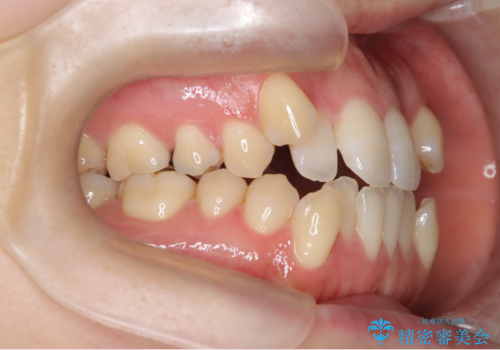

- 前歯のガタガタや八重歯の位置の乱れが気になっていた患者様に対して、ワイヤー矯正を行いました。矯正の過程で、スペースを確保するために上下左右の小臼歯を抜歯し、歯全体のバランスと機能性を考慮しながら理想的な歯列に仕上げました。

抜歯によって確保したスペースを活用し、効率的に歯列を整えました。前歯のガタガタと八重歯が解消され、自然で美しい仕上がりを実現しました。